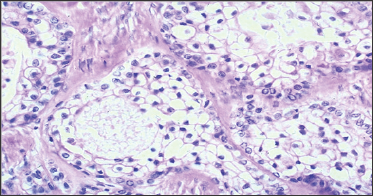

The cells showed moderate to abundant granular pale eosinophillic cytoplasm. Nuclei were vesicular with open chromatin pattern and occasional mitotic filling. Histological diagnosis was established as "Clear Cell Odontogenic Carcinoma". Therefore, the patient underwent wide local resection with hemi-mandibulectomy and modified radical neck dissection under general anesthesia. The resected specimen was sent for histopathological and immuno- histochemical evaluation with demarcation of surgical margins. The report showed the lesion measuring up to 4 x 3cm with tumor free resection margins. Three out of the 15 neck nodes revealed metastases, with the largest lymph node measuring 0.4 x0.3cm. Microscopically, tumor cells infiltrating the bony trabeculae were arranged in form of nests having moderate amount of eosinophillic cytoplasm, with small round to oval nuclei (Figure 3). In few areas of cytoplasm neoplastic cells appear clear. No extra-capsular extension or perineural invasion was seen. Immune histochemistry revealed focal positivity for intra cytoplasm glycogen on special stain (PAS with Diastase) and diffuses positivity for cytokeratin (AE1/AE3 immuno-histochemical stain). Patient recovery was uneventful and the patient is under regular follow up.

Figure 3: Histopathology, Microscopic Image.

This microscopic slide shows fibrous tissue exhibiting an infiltrating lesion composed of masses and small aggregates of polygonal cells with moderate to abundant granular pale eosinophillic cytoplasm. Nuclei are vesicular with occasional mitotic filling.